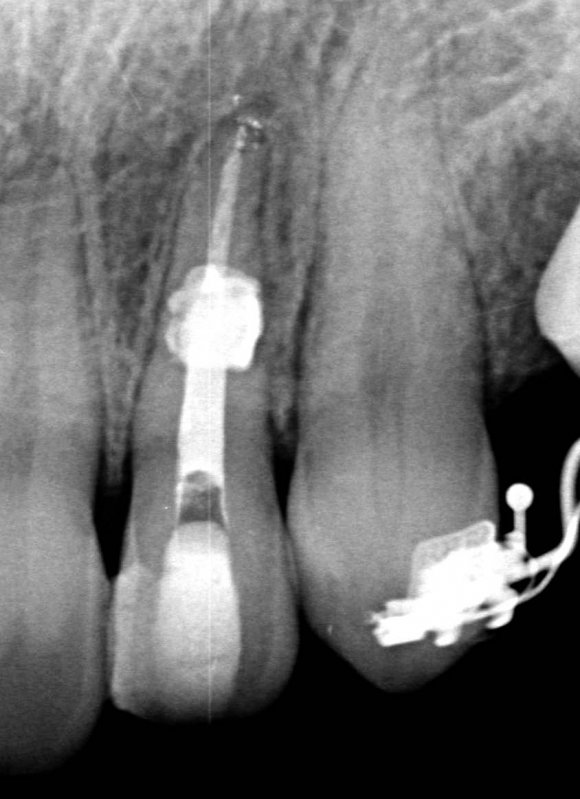

The X-ray snapshots showed signs of internal resorption in tooth 2.2.

The CBCT revealed intraroot perforating resorption on the vestibular root surface. In addition, a possible cause of resorption was identified as Oehlers' Type I invagination (1957), which was based on the radiological findings. According to the classification, Type I invagination is covered with enamel and is located within the coronal part, extending no further than the enamel-dentin junction. The authors believe that the infected invagination zone with subsequent creeping infection of the root pulp brought about the resorption. The response to the cold stimulus was very insignificant, especially in comparison with tooth 12. This made it clear that an irreversible destructive process is going on in the damaged tooth. Since the patient was planning orthodontic treatment and the resorption process could grow worse, it was decided to conduct endodontic treatment.

Also, there were signs in favor of internal resorption. The defect was below the cervical part, which is not typical of external cervical resorption. The response to cold stimuli reduced, which is not characteristic of external resorption, as it affects the pulp only in the last stages of tooth structures decay. Furthermore, the X-ray obliteration of the root canal beyond the resorption area is not characteristic of external resorption. Visit 1: Pre-op X-ray plus anesthesia with sol. Ubisthesini 4% -1 ml, isolation with rubberdam. The access was made as close as possible to the incisal edge. When opened, at first glance the pulp chamber looked quite II.